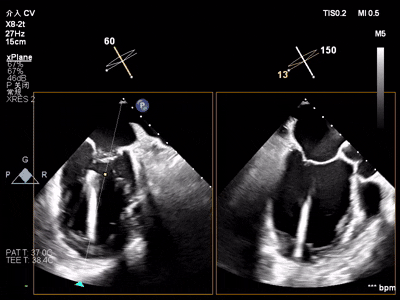

【术中操作(含关键步骤超声)】

鉴于患者术前心功能差、多支架植入的特殊情况,手术全程需兼顾“精准操作”与“保护心功能”双重要求:在全麻与经食道超声的协同引导下,团队先突破心功能受损导致的术野稳定性难题,稳步经心尖建立手术轨道与输送鞘;随后聚焦二尖瓣2偏3区精准置入一枚Ⅱf型夹合器,成功攻占这一解剖位置深、毗邻结构敏感、容错率极低而操作难度陡增的区域。

手术中,主刀术者常青教授稳定发挥,经过严谨的策略思索,挑战超精细微调整与瞬间捕获夹合,逐步逆转反流症状。从显著改善到最终完全消除,全程仅约25min的导管操作时长。在高危病例的严苛挑战下,凸显了团队操作的娴熟度与安全性。

术前术后反流对比

【术后一周复查心超提示】二尖瓣钳夹术后,二尖瓣反流(轻度),夹合器固定,瓣口呈双孔结构,内外侧孔分别见微量反流,反流束VC分别 0.15cm、0.18cm,估测有效瓣口面积约2.5c㎡,舒张期瓣口前向最大血流速度 1.2m/s,平均压差3mmHg,左室射血分数(EF)值提升至35%,心功能显著改善。目前患者已顺利康复出院。